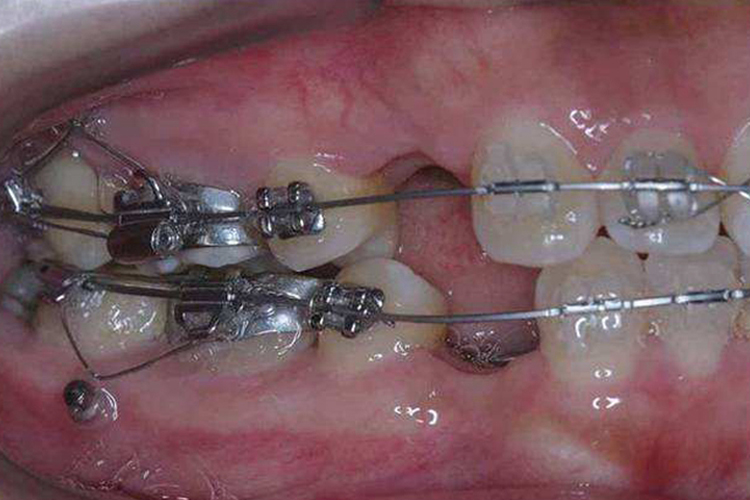

种植体支抗是在两个中切牙之间置入一种植钉,借助悬吊力量压低前牙,还可将种植钉置入侧切牙与尖牙之间的骨中隔上,借助弹簧、皮链或弹力线与前牙连接,可直接压低前牙。